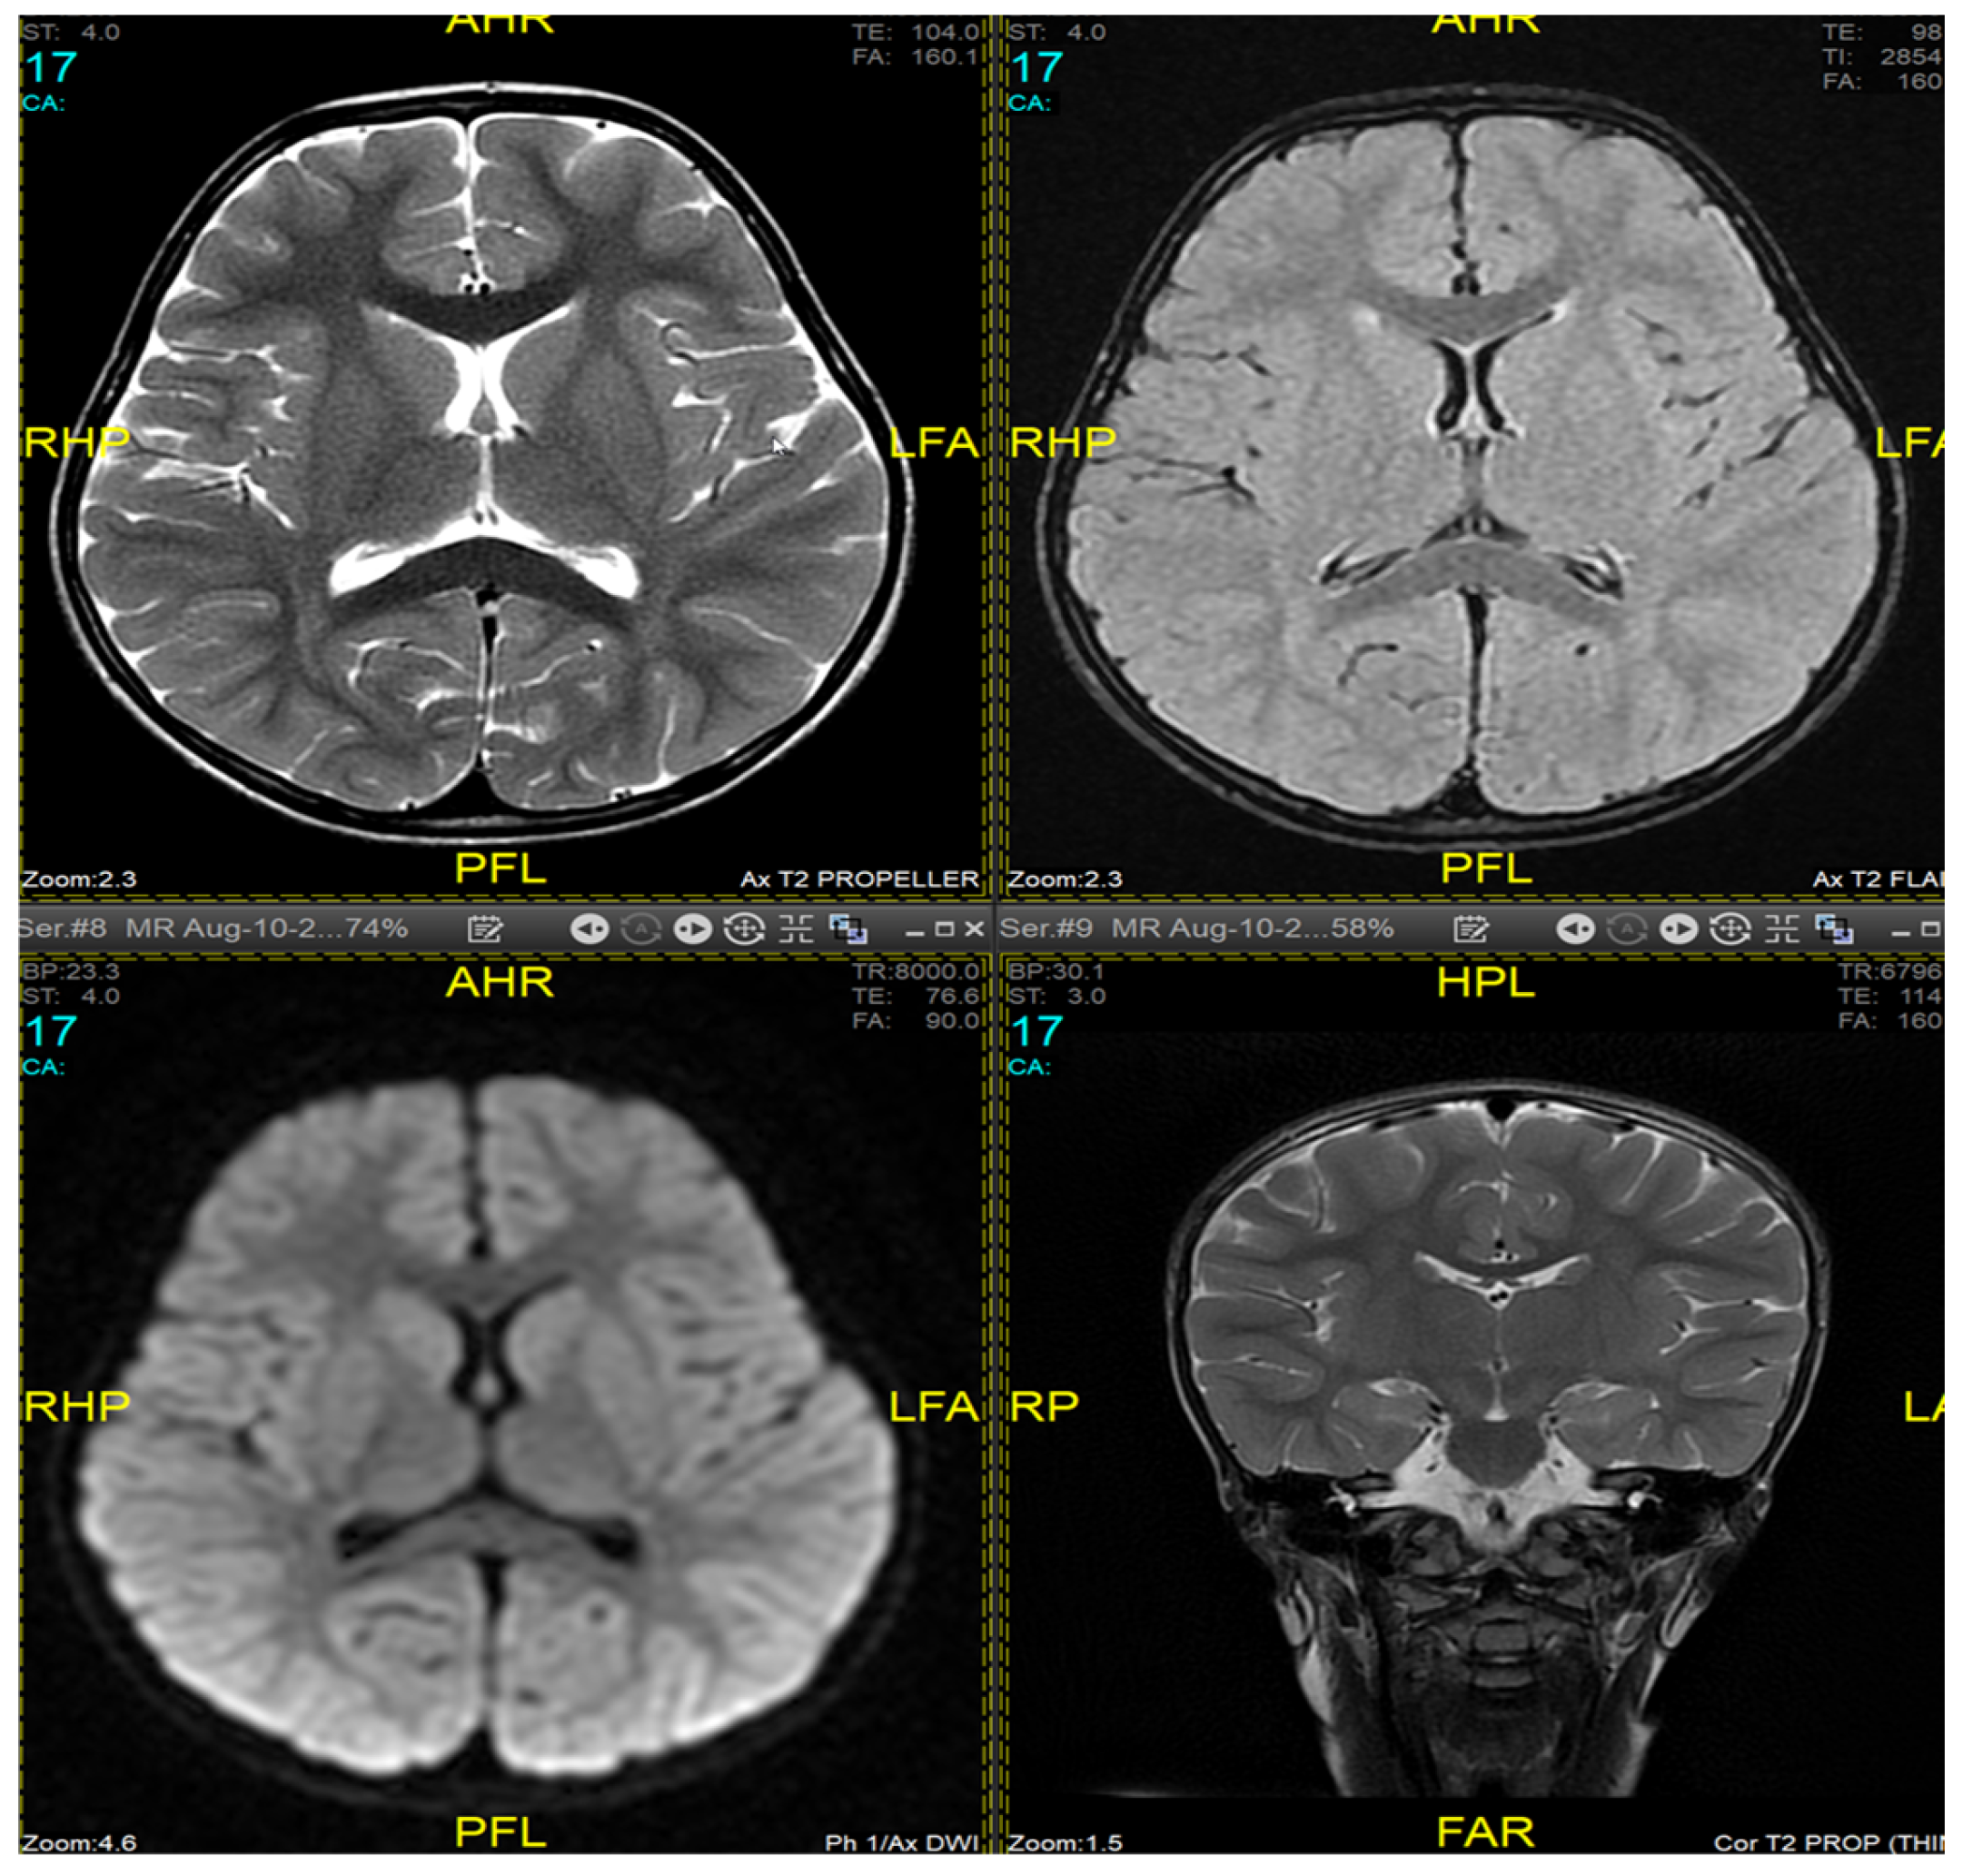

Magnetic resonance imaging (MRI) of the brain and genetic analysis were performed to support the diagnosis. Her MRI showed newly developed generalized atrophic changes of the brain, characterized by supra and infratentorial ventricular dilatation, prominent cortical sulci, and extra-axial CSF spaces such as Sylvian fissures and basal cisterns. The diffuse deep periventricular white matter showed high signal intensities on T2/FLAIR (fluid-attenuated inversion recovery) sequences. Additionally, there was global thinning of the corpus callosum [Figure 1]. This was in contrast to her prior brain MRI at 2.5 years old, which showed no evidence of atrophic brain changes or iron deposition [Figure 2].

Figure 2.

Brain MRI at 2.5 years old (10 August 2017). No evidence of atrophic brain changes or iron deposition.

MRI findings are variable depending on the disease stage at which imaging was performed [1,3,10,12]. Imaging may be completely normal in some patients, as was the case in our patient during the first presentation, making it insufficient to rule out INAD based on radiological findings only and necessitating follow-up imaging later. Typical findings described include cerebral atrophy, white matter changes, and iron deposits in the globus pallidus, substantia nigra, and dentate nucleus [19,20]. Due to the presence of iron deposits, INAD can be classified as a subtype of neurodegeneration with brain iron accumulation diseases (NBIA). The alteration of mitochondrial functions may affect mitochondrial iron homeostasis, leading to neurodegeneration [21]. Defects in transferrin receptor recycling were established to be a common anomaly in fibroblasts from different subtypes of NBIA patients [22], suggesting impaired iron incorporation as a shared mechanism responsible for iron overload in these pathologies. However, iron deposits are not specific to INAD [23]. Our patient exhibited typical MRI features in a follow-up study but did not have any evidence of iron accumulation in the brain.